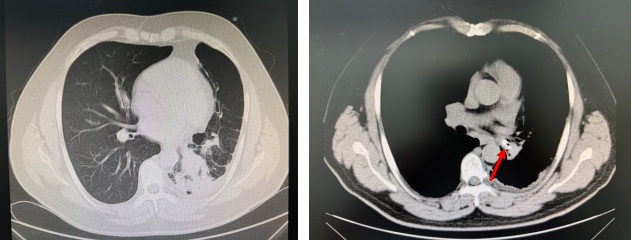

今年49岁的张先生(化名)长期饱受咳嗽、咳痰、呼吸困难的折磨,曾多次在外地医院治疗,效果不佳。近期症状加重,慕名来到哈医大一院群力院区呼吸内科于世寰教授处就诊。肺部CT检查结果令人惊讶:患者左侧气胸、左肺下叶支气管内存在可疑高密度异物阴影,并伴有阻塞性肺炎,遂急收入院。

手术当天,于世寰主任医师、李世敏副主任医师在全身麻醉保障下为患者进行手术。术中发现,患者左主支气管远端因长期异物刺激,已形成大量肉芽组织增生及瘢痕,导致管腔严重狭窄,大量脓性分泌物淤积。清除脓液后,镜下可见部分异物,但因管腔狭窄(直径小于4.2mm支气管镜),常规方法难以取出。李世敏医生谨慎运用氩气刀、电凝棒及活检钳等设备,耗时近3.5小时,逐步清除覆盖在异物周围的增生肉芽组织和瘢痕(术中需精细操作以避免出血),最终成功利用异物钳取出一枚完整的塑料笔帽。